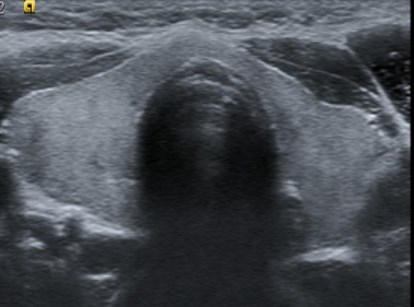

cuando hacemos un tiroidectomizado, vemos esto:

Quiero que veas las dos imágenes y compares.

Lo más importante, saber cómo es la «normalidad» de una región tiroidectomizada, te la dejo en las dos siguientes imágenes, veremos una zona hiperecogénica correspondiente a la grasa que ocupa el espacio que ya no ocupa el tiroides. Cuando el paciente es diagnosticado de ca de tiroides suele realizarse tiroidectomía total.

Una vez conocida la normalidad relativa de esta arquitectura anatómica volvemos al hallazgo, que como puedes comprobar tiene aspecto nodular, hipoecogénico, de bordes mal definidos y eventualmente, como es el caso de la imagen siguiente (corte longitudinal), tiene microcalcificaciones, semiología ésta de altísimo grado de sospecha.

La semiología del tejido normal que puede crecer en el lecho quirúrgico, lo denominado anteriormente como «restos tiroideos» es una ecoarquitectura mucho más amable y más parecida al tejido tiroideo normal, hiperecogénico, bordes respetados aunque irregular, homogéneo…